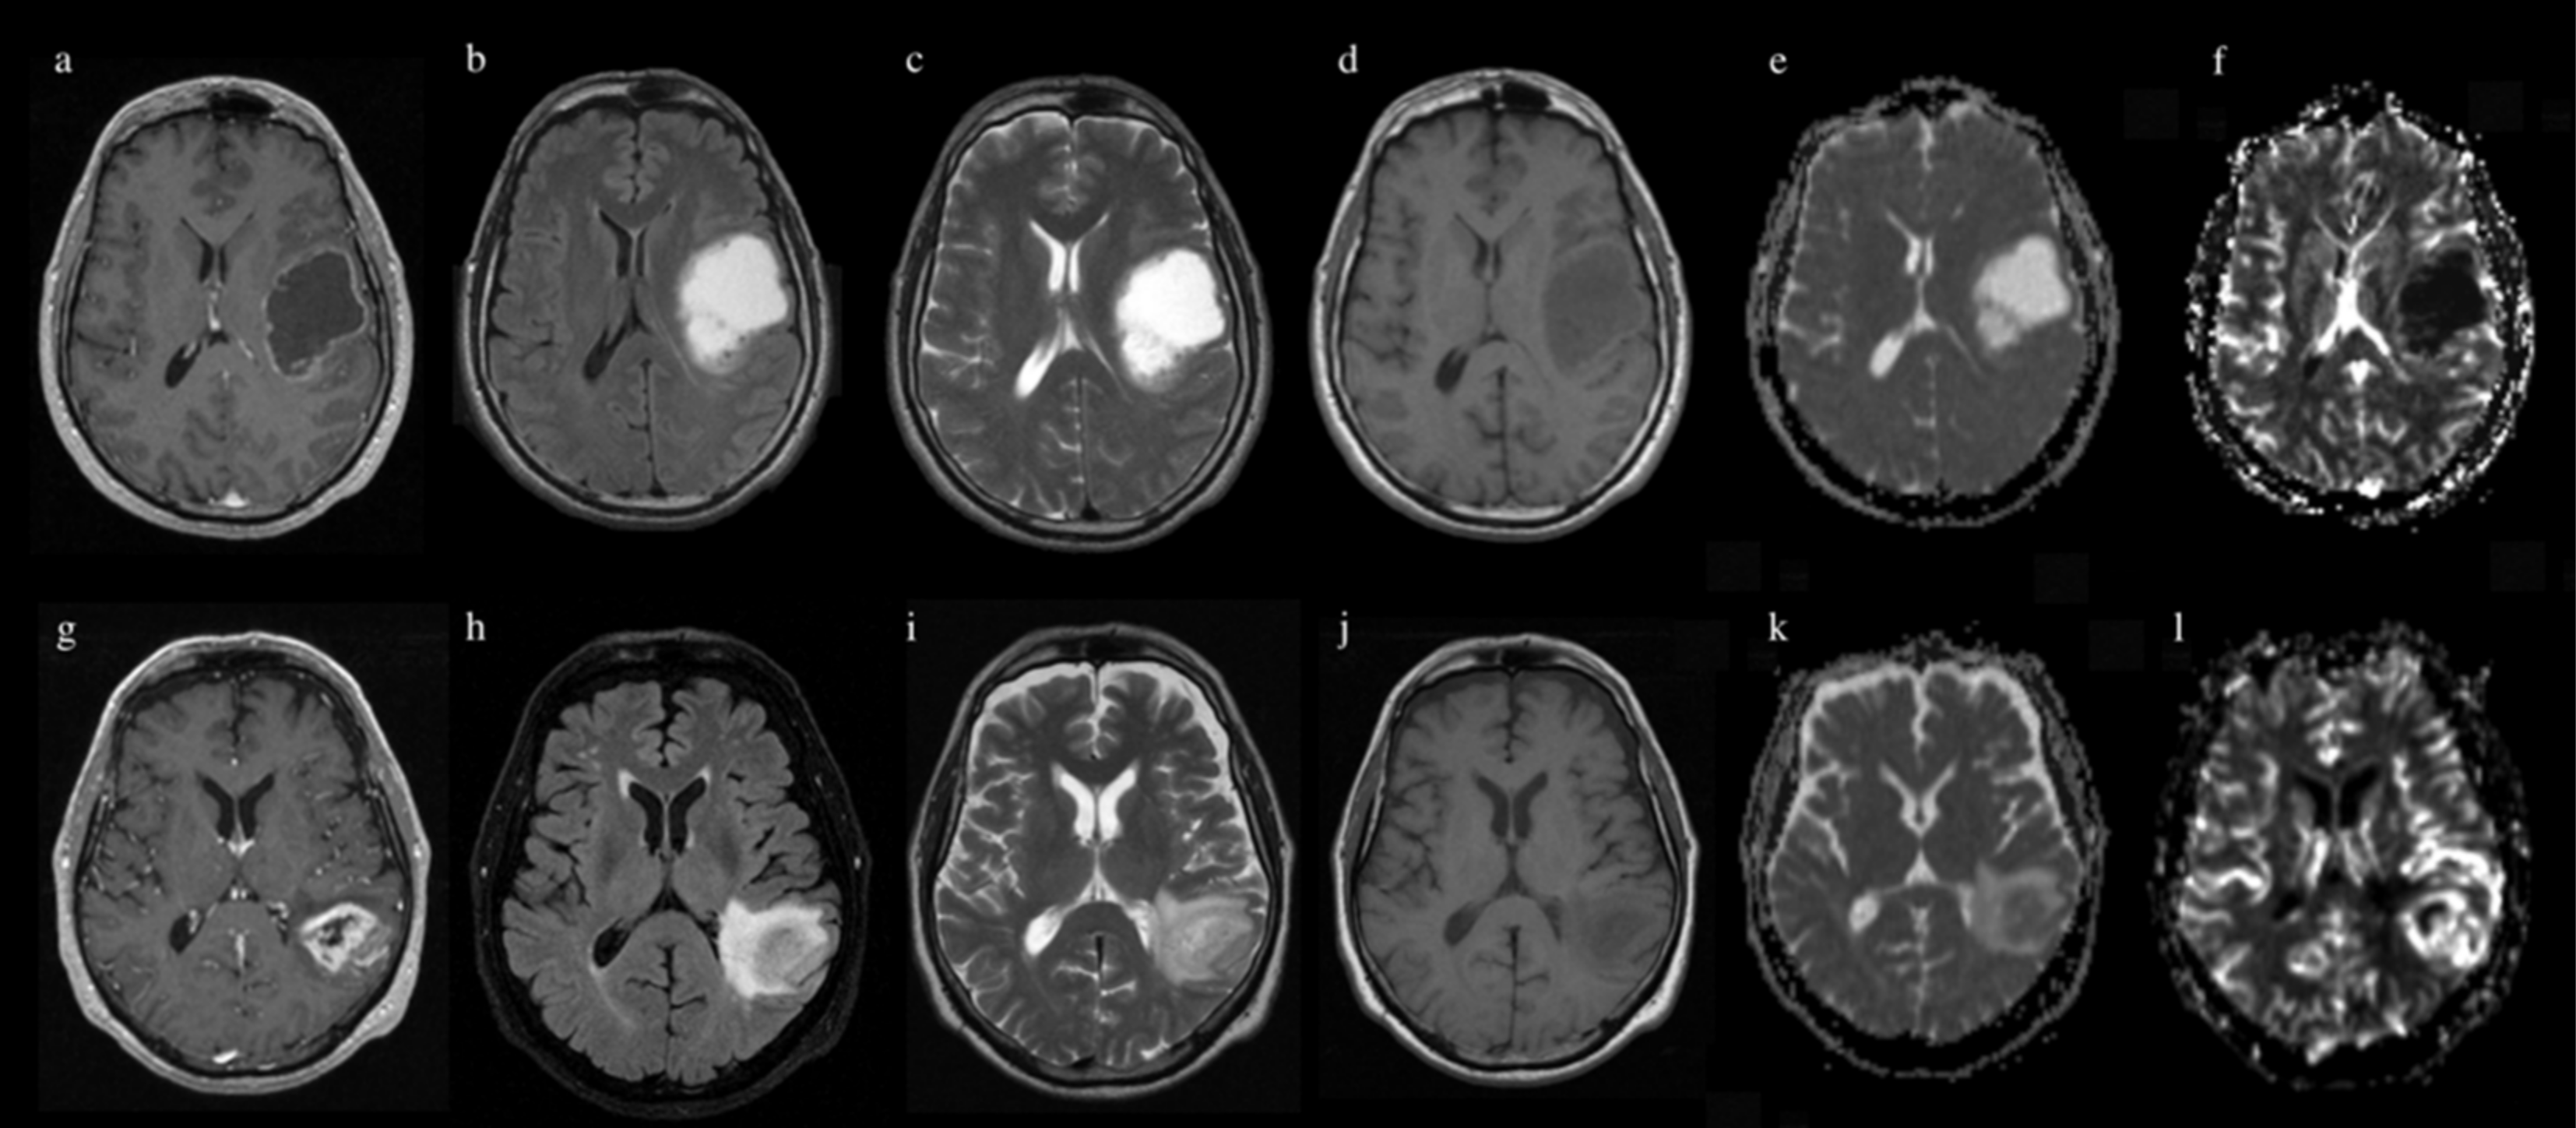

2. Materials and Methods

2.3. MR Image Acquisition

2.4. Image Processing

| rCBV | 0.83 ± 0.07 | 0.64 ± 0.23 | 0.76 ± 0.08 | 0.86 ± 0.08 | 0.86 ± 0.05 |